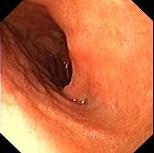

问题 女,36岁,上腹痛2年,伴嗳气、呃逆,弯腰时加重,查体未见特殊。胃镜如图,钡餐未:可见左侧隔上囊状阴影。最可能的诊断是 ( )

选项 A.食管裂孔疝 B.胆石症 C.消化性溃疡 D.幽门梗阻 E.反流性食管炎

答案 A